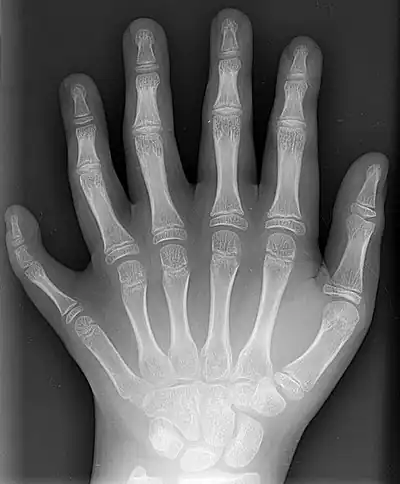

X-ray showing joints- Hand bone anatomy

The skeleton of the human hand consists of 27 bones:[10] the eight short carpal bones of the wrist are organized into a proximal row (scaphoid, lunate, triquetral and pisiform) which articulates with the bones of the forearm, and a distal row (trapezium, trapezoid, capitate and hamate), which articulates with the bases of the five metacarpal bones of the hand. The heads of the metacarpals will each in turn articulate with the bases of the proximal phalanx of the fingers and thumb. These articulations with the fingers are the metacarpophalangeal joints known as the knuckles. At the palmar aspect of the first metacarpophalangeal joints are small, almost spherical bones called the sesamoid bones. The fourteen phalanges make up the fingers and thumb, and are numbered I-V (thumb to little finger) when the hand is viewed from an anatomical position (palm up). The four fingers each consist of three phalanx bones: proximal, middle, and distal. The thumb only consists of a proximal and distal phalanx.[11] Together with the phalanges of the fingers and thumb these metacarpal bones form five rays or poly-articulated chains.